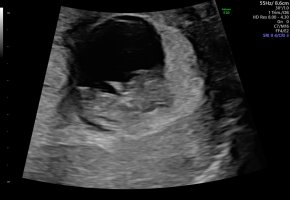

Det viktigste er at alt sto bra til. Målt en dag lengre fram, men siden dette er ivf så kan ikke dato endres etter størrelse

Nå kan denne overnervøse mammaen roe seg litt ned igjen